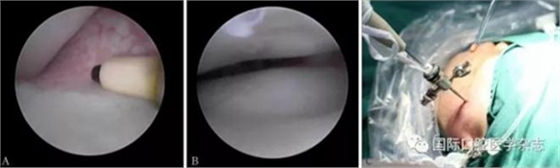

(1)顳下頜關(guān)節(jié)鏡微創(chuàng)治療。使用關(guān)節(jié)鏡治療的適應(yīng)證:顳下頜關(guān)節(jié)紊亂病,保守治療效果不佳,病情較重者(圖17)。2)顳下頜關(guān)節(jié)盤復(fù)位錨固術(shù)(圖18)。使用顳下頜關(guān)節(jié)盤復(fù)位錨固術(shù)治療的適應(yīng)證:顳下頜關(guān)節(jié)紊亂病,保守治療無效,關(guān)節(jié)鏡手術(shù)效果不佳者。

A:射頻刀松解黏連帶;B:復(fù)位后的關(guān)節(jié)盤;C:關(guān)節(jié)鏡術(shù)中。

圖 17 關(guān)節(jié)鏡手術(shù)